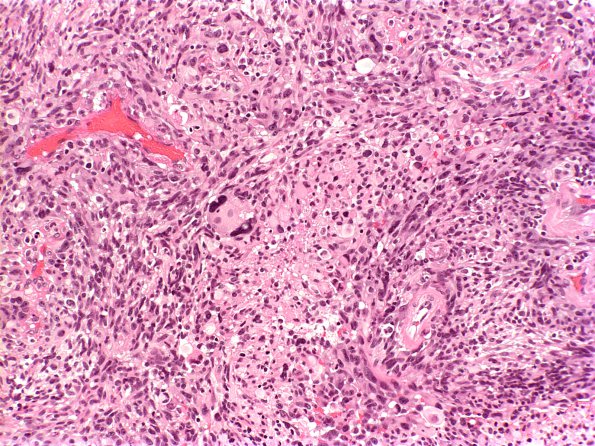

Washington University Experience | NEOPLASMS (GLIAL) | Gliosarcoma | 6A1 Gliosarcoma (Case 6) H&E 1

Case 6 History ---- The patient is a 56 year old man with a right frontal lobe neoplasm. ---- 6A1-3 Sections reveal a highly anaplastic-appearing neoplasm with marked nuclear pleomorphism. The cells range from spindled to epithelioid, often with extensive eosinophilic cytoplasm, vesicular chromatin and prominent nucleoli. (H&E)